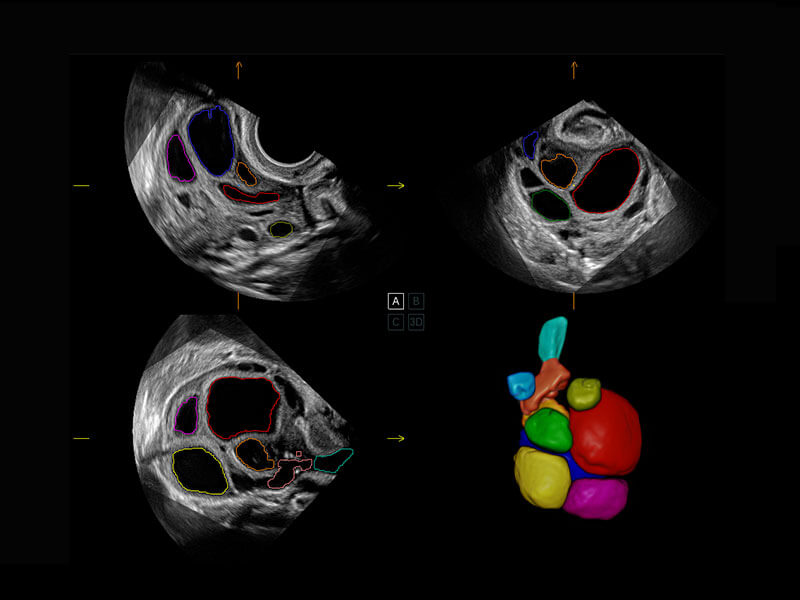

P60搭载一系列胎儿心脏成像技术,实现精细的胎儿心脏评估。

胎心容积成像